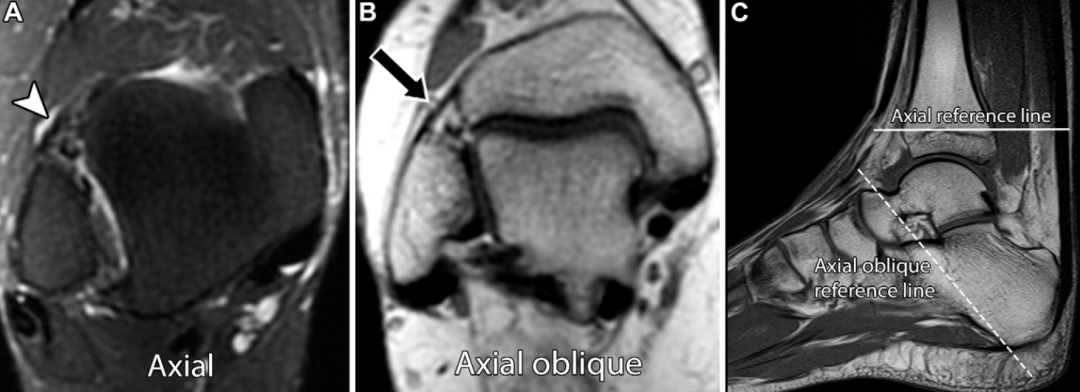

下胫腓前韧带和下胫腓后韧带与正交平面呈斜行走向,在常规轴位MRI上可能被误判为撕裂。常规踝关节斜轴位MRI序列的扫描平面,需在矢状位定位像上垂直于腓骨肌腱,沿肌腱从踝后至足中段的走行方向设定。本文作者认为,该序列有助于评估下胫腓前韧带和下胫腓后韧带,对下胫腓前韧带的评估效果尤为显著:

三维各向同性涡轮自旋回波序列为评估远端胫腓联合提供了可靠方法,该序列具有高信噪比和对比噪声比,可进行多平面重建,包括45°斜位评估,其对急、慢性胫腓联合损伤的诊断效能与二维质子密度加权MRI相当。尽管三维SPACE序列(基于不同翻转角演化的优化对比采样完美序列)的图像边缘清晰度低于二维涡轮自旋回波序列,但其能清晰显示韧带的连续性、轮廓和信号强度,可实现准确诊断,对急性损伤的诊断尤为适用;对于慢性损伤,斜位成像可提升韧带形态的显示效果,有助于损伤分型。